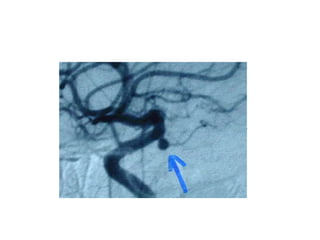

ANGIOGRAFIA

DE

PREFERENCIA

ANGIOTEM

ANGIORNM

DIAGNOSTICO DE ANEURISMA

EXAMENES DE DIAGNOSTICO TOMOGRAFIACEREBRAL SIN CONTRASTE ANGIOGRAFIA DE PREFERENCIA